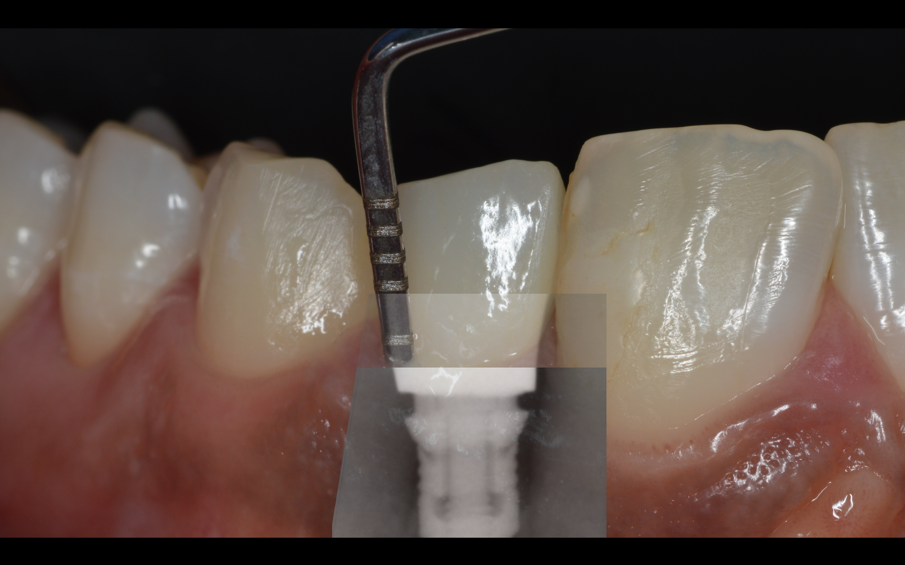

Dopo 3 mesi la situazione dell’abutment, una volta smontato l’healing abutment, è di quelle desiderabili in una protesi su impianti (Fig. 15). Terminato il lavoro con la consegna del manufatto protesico, si procede con la spiegazione, in vari appuntamenti delle manovre di igiene per il corretto mantenimento del lavoro nel tempo. Per la rimozione di placca batterica fresca si istruisce il paziente all’utilizzo di super floss per la detersione nella zona confine tra protesi e tessuti molli (Fig. 16). Super floss di oral-b è utilizzato anche per le manovre di igiene orale in studio per l’igiene dei monconi implantari.

Fig. 8_Curettaggio manuale con strumenti dedicati.

Fig. 9_Punte ultrasoniche in Peek.

Fig. 10_Rimozione della placca con strumenti in Peek che non rovinano l’abutment.

Fig. 15_Ottimo stato di salute di OT Bridge allo smontaggio della vite di guarigione.

Fig. 16_Manovre di igiene domiciliare con superfloss.